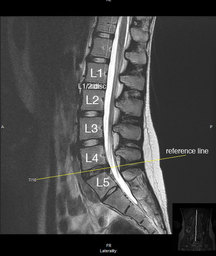

MRI is the standard of care when it come to identifying disc herniations and complete ligament ruptures (Grade 3) such as the ACL. So when looking for disc injuries keep in mind that statistically speaking, the vast majority of herniations occur the lumbar spine.

Magnetic Resonance Imaging (MRI) is one form of imaging used by physicians to look inside the human body to obtain clinically useful diagnostic information. Images are formed when signals emitted by body tissue are processed and turned into visual clinical images.